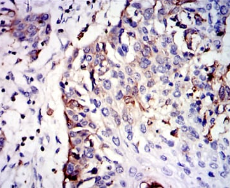

GSTM1 Mouse Monoclonal antibody[1H4F2]

IHC    1/200 - 1/1000